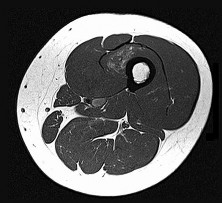

This patient has a dedifferentiated liposarcoma within a preexisting atypical lipomatous tumor. The imaging demonstrates a large fatty mass with increased internal septations proximally (the atypical lipomatous tumor) and a solid enhancing mass distally (the dedifferentiated portion). A biopsy reveals a high-grade liposarcoma. The other diagnostic responses do not reflect sarcomatous transformation of the lesion.

Surgical treatment of a high-grade sarcoma involves wide surgical resection. Radiation decreases local recurrence but does not clearly influence overall survival. The role of chemotherapy in high-grade soft-tissue sarcomas remains investigational; there is a modest (8%-15%) associated improvement in overall survival.

Intramuscular lipomas and atypical lipomatous tumors are treated with marginal resection alone. Radiation therapy for soft-tissue sarcomas may be given before or after surgery. When administered before surgery, patients have a higher wound complication rate but better long-term function attributable to lower rates of lymphedema, fibrosis, and contractures.